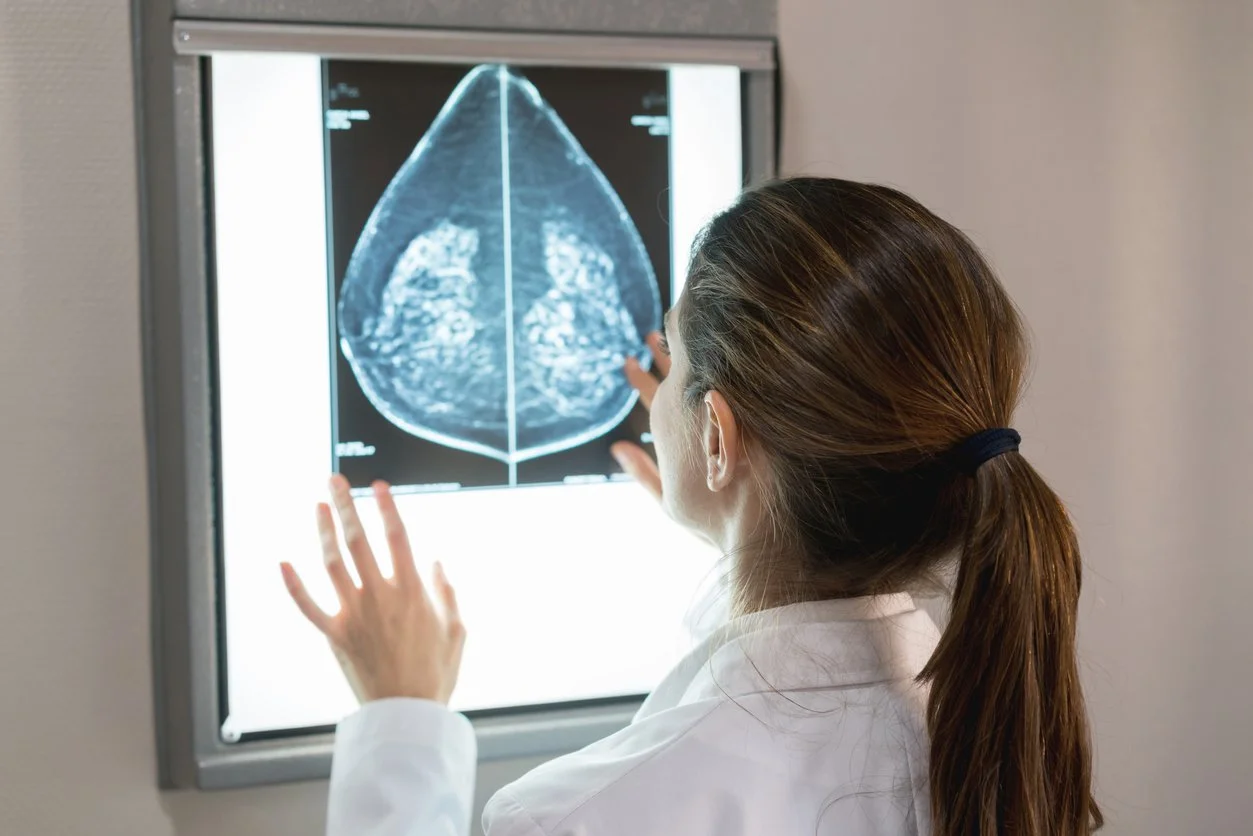

For the past 6 years, I've faithfully undergone annual screening mammograms, consistently encountering the phrase "very dense breast tissue" in my results. This classification, while common, complicates the screening process as it can obscure the radiologist's view, making it difficult to detect early signs of breast cancer through mammograms alone. Despite this limitation, I adhered to the recommended protocol of annual x-ray mammograms, understanding their limitations but valuing the importance of regular check-ups. However, the landscape of breast cancer screening has evolved. In 2023, the FDA began requiring education and documentation of very dense breasts [1]. While there are no formal recommendations, the data is clear that MRI is superior in detecting breast cancer earlier in women with very dense breast tissue. This year, I was able to advocate for myself and I received a breast MRI, which is known to enhance my breast cancer detection.

Breast density is a significant factor in breast cancer screening and risk assessment, classified into four categories by radiologists: A, B, C, and D. Categories A and B indicate breasts that are mostly fatty, while C and D denote progressively higher densities, with D being the densest. Dense breasts, particularly in categories C and D—which include about half of all women and specifically 10% in category D alone—pose challenges for detection using traditional mammography. This is because both dense tissue and tumors appear white on a mammogram, making it difficult to differentiate between the two. As a result, women with category D breasts face a twofold to fourfold increased risk of developing breast cancer, independent of other risk factors.

Magnetic Resonance Imaging (MRI) of the breast is a sophisticated diagnostic tool that uses powerful magnetic fields and radio waves to generate detailed images of the breast tissue. Unlike mammography, which relies on X-rays, breast MRI isn't impeded by dense tissue, allowing for a clearer and more comprehensive view of the breasts.

The Procedure: What to Expect during a Breast MRI